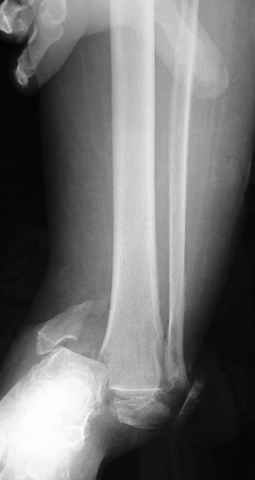

Еще, кстати, о фиксации лодыжки, если уж непременно хочется ее отдельно стабилизировать - при таком характере перелома замечательно должен сработать предложенный проф. Лазаревым с соратниками способ фиксации напряженной V-образной спицей. Опять же, открытая репозиция не нужна, мы делаем непрямую репозицию именно аппаратом. В приложении пример, там перелом малоберцовой куда менее поперечный, чем в данном случае, но все равно получилось закрыто без пластинки.

I can't realize why plate fibula separately if anyway external fixator including the foot is planned, i.e. one may insert wires to the talus, calcaneus, lateral malleolus and anywhere else. Plating looks reasonable if only temporary ex-fix is planned, but in the case it will be definitive.

A propos fibular fixation if one is eager to stabilize it separately. In the fracture pattern a way of closed fixation by V-shaped stressed wire (advanced by colleagues from Moscow, prof. Lazarev A.F. et al.) must be excellent. We use indirect closed reduction by the external fixator. Example attached, that fibular fracture is even more suitable for plating but the wire did the job.